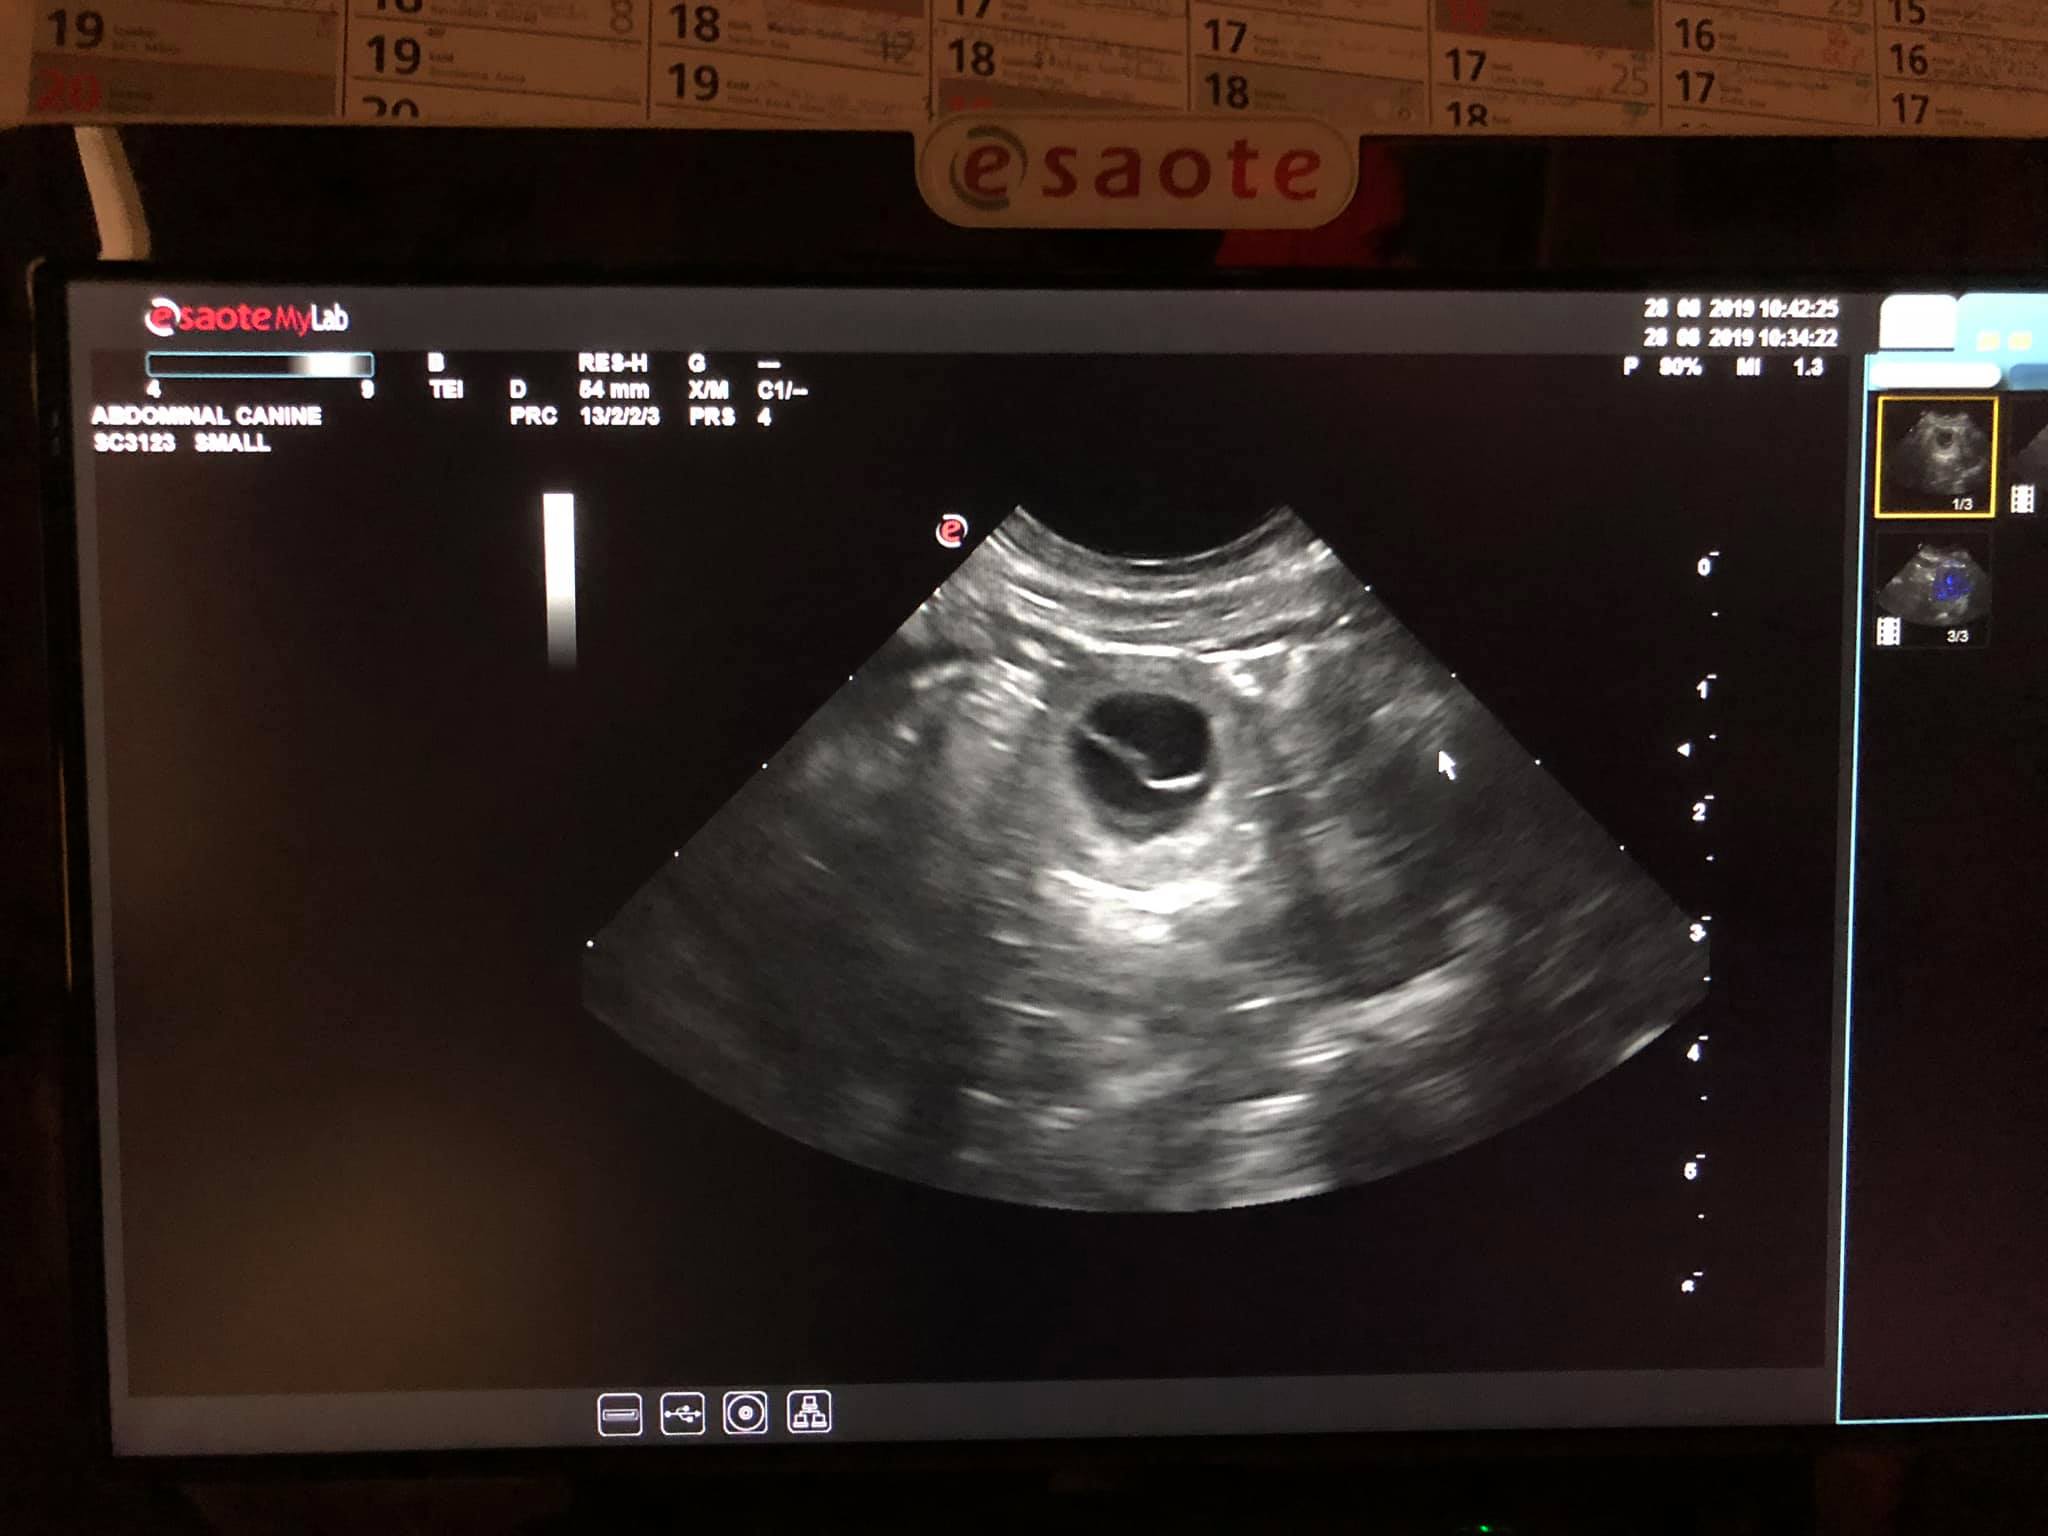

Ultrahang 2019.08.28.

A mai napon ellátogattunk az Ani-Rep Szaporodásbiológiai Szakrendelőbe, ahol nagyon jó híreket kaptunk. Nina hasában 5-6 kölyök növekszik!

Ma tartunk a 25. napnál:) Hamarosan további részletekkel jelentkezünk!

Addig is egy kép az egyik kicsiről, ugye milyen szép?